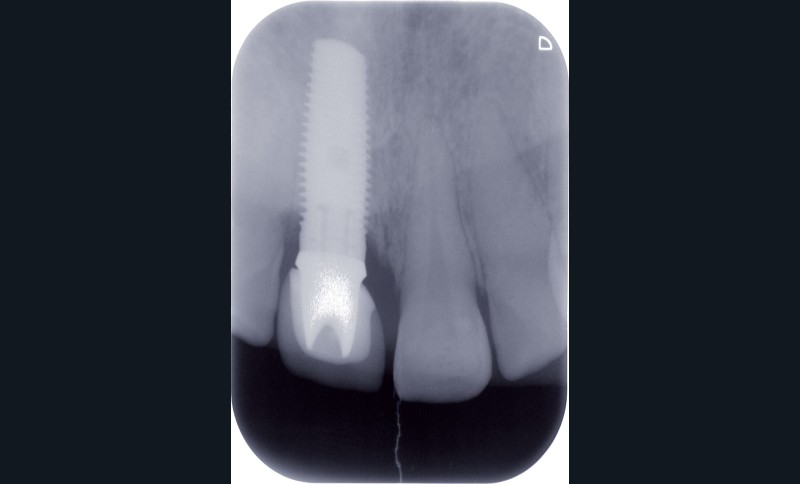

Une patiente âgée de 28 ans consulte pour un problème esthétique au niveau de la dent 11, porteuse d’une couronne implanto-portée (fig. 1a).

L’examen clinique révèle une différence d’alignement et un tissu gingival péri-implantaire peu épais sur cette couronne implanto-portée.

La radiographie ne révèle aucun problème d’ostéointégration implantaire (fig. 1b).